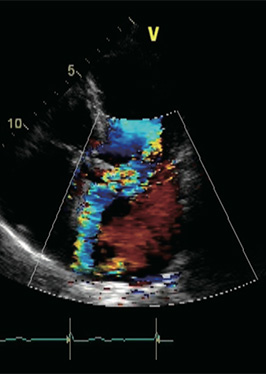

【講  演】 心エコー図法を臨床に活かす。リスク層別化とHFpEF対策

講師 : 岡山大学大学院医歯薬学総合研究科

循環器内科学 教授 伊藤浩 先生